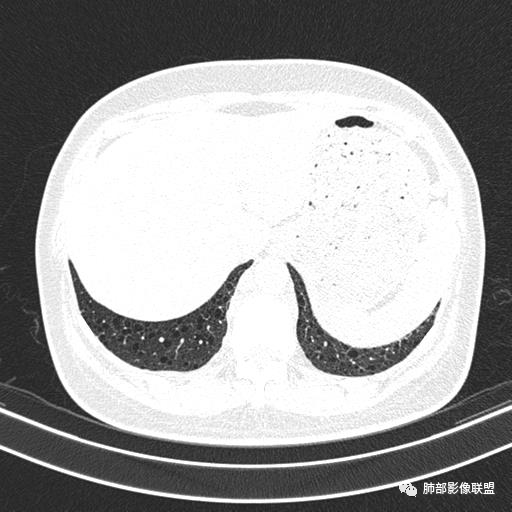

CT平扫示双肺弥漫分布大小不等囊状薄壁透光区,无内、中、外带分布差异,间质稍示增厚。拟LAM

女,46,活动性气喘1年。苯吸入史半年。胸部CT:两肺弥漫囊腔,上至肺尖,下至肋膈角,形态类似小囊腔。考虑:LAM,鉴别LIP,BHD,PLCH等。

CT表现:双肺弥漫大小不等的薄壁囊腔,囊壁<2mm,外形规则,血管影多位于囊腔周围,囊腔之间肺组织正常,随着疾病进展到晚期,囊腔变大、增多,不可胜数,囊腔可融合成较大的囊,与肺气肿相似,形成间质性肺纤维化。部分病例可出现结节影。